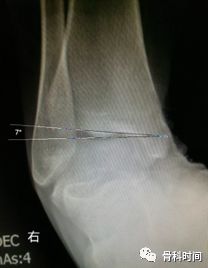

生活中,崴脚后常常忽视外固定的作用,特别是未存在撕脱骨折以及 X 线片假阳性者,踝关节应力位 X 片对于单纯的韧带损伤可发现踝关节不稳。

距骨倾斜角:内翻应力正位片中距骨相对于胫骨远端关节面倾斜角度≥9°,即可考虑踝关节不稳,但此时应考虑患者的职业,如芭蕾舞演员可存在足踝部韧带松弛

30 岁青年女性,1 年前右踝首次发生崴脚,未行外固定,伤后右踝间断数次崴脚,双侧踝关节应力正位片测量距骨倾斜角,左侧为 0°,右侧 7°,右侧虽尚不能诊断踝关节不稳,但距骨倾斜角增大,对比对侧仍考虑为崴脚后未外固定所致。